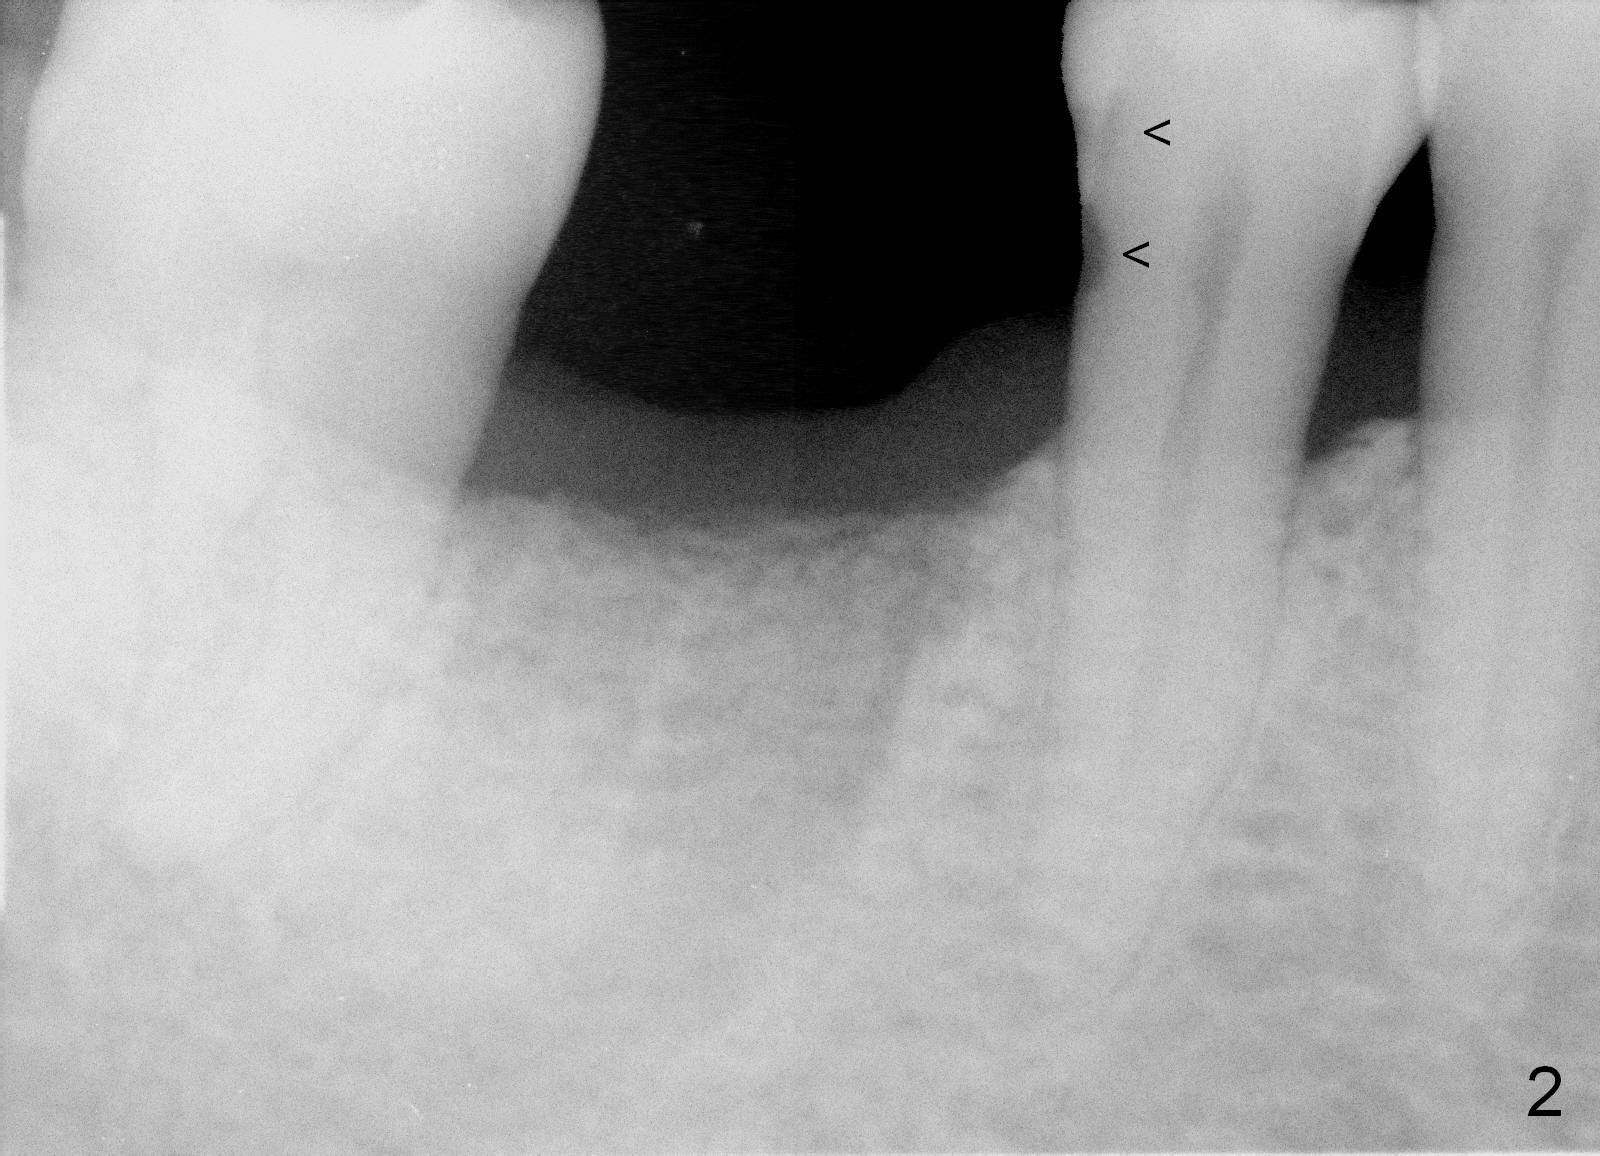

A 44-year-old man lost the tooth #30 three months ago. He is very nervous about the Inferior Alveolar Nerve (Fig.1,3 yellow dashed line). Offer Valium if needed. Check whether there is DO caries of the tooth #29 (Fig.2 <). Finish composite if indicated. There is mild to moderate buccal plate atrophy. The implant may have to be placed slightly lingually. When the insertion torque is high, place an abutment (Fig.3 white inverted cup) with subgingival margin (arrowheads: gingival margin) so that the emergency profile of the crown is better. Make an ideal immediate provisional with good emergency profile and place sutures. The mesial bone may have to be trimmed (Fig.4 red area) so that the abutment is able to be seated without interference. Take photo at each step.